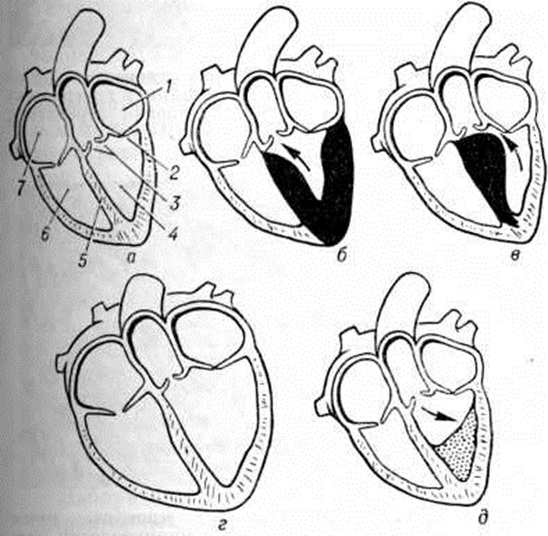

На рисунке 1 видно различие между тремя формами Кардиомиопатии Гипертрофическая Кардиомиопатии функционально характеризуется сопротивлением кровенаполнению желудочков в диастоле, анатомически — резкой гипертрофией желудочков (главным образом левого) и значительным уменьшением объёма полости желудочка. При застойной Кардиомиопатии снижается систолическая насосная функция сердца в результате диффузного поражения миокарда и выявляется неспособность желудочка к достаточному опорожнению в систоле; анатомически застойная Кардиомиопатии характеризуется резкой дилатацией желудочков, часто маскирующей небольшую степень гипертрофии, поэтому её называют иногда дилатационной формой Кардиомиопатии Облитерирующая Кардиомиопатии анатомически характеризуется избыточным развитием соединительной ткани в правом или левом желудочке в области верхушки сердца с плотным фиброзом стромы миокарда.